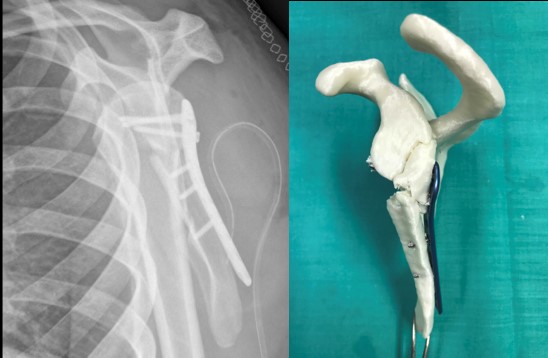

En esta ocasión, se trata de una fractura de escápula en la que se ha aplicado la tecnología de Impresión 3D para su tratamiento por parte del Dr. Fernando García de Lucas y su equipo de Cirugía Ortopédica y Traumatología del hospital FREMAP de Majadahonda.

Gracias a esta técnica e inicialmente sobre la impresión de 3D a escala real, se llevó a cabo la reducción de la fractura y la fijación interna, con la misma placa con la que se realizó el tratamiento definitivo.